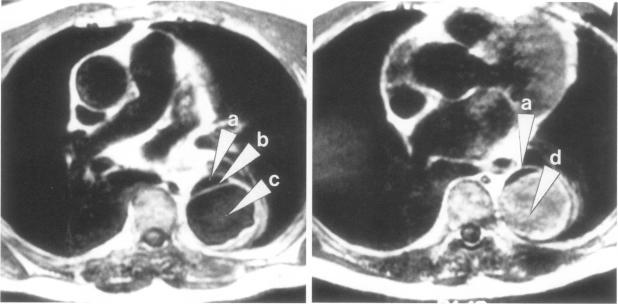

Magnetic resonance imaging is an excellent noninvasive method for evaluating thoracic aortic dissections. A variety of magnetic resonance scans of aortic dissections are shown, documenting the ability of magnetic resonance to image the true lumen, the false channel, and the intimal septum. Detail is provided on magnetic resonance imaging techniques and findings.

磁共振成像是评估胸主动脉夹层的一种出色的非侵入性方法。展示了各种主动脉夹层的磁共振扫描图像,证明了磁共振对真腔、假腔和内膜隔膜成像的能力。文中提供了磁共振成像技术及结果的详细信息。